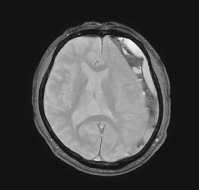

2台のMRIにはGE最新のAI技術とTDI (Total Digital Imaging)を組み合わせ、質の高い画像撮影とディープラーニングを使用しての画像作成により高画質で検査時間も短縮出来る機器を揃えています。自覚症状の無い脳梗塞、脳出血、脳動脈瘤等から全身の症状が現れるまで発見出来ない様な病変の診断を可能にします。

MRI検査

内科領域